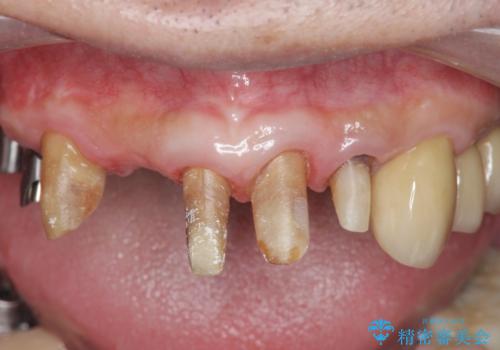

歯周病治療を伴う前歯審美セラミック治療

- 前歯の見た目をなんとかしたい、とセラミック治療を希望され来院されました。

セラミック治療を行う前に歯周病の問題を解決すべく歯周外科を行い歯周ポケットを除去し整備したのちセラミックブリッジ・クラウンの製作を行います。